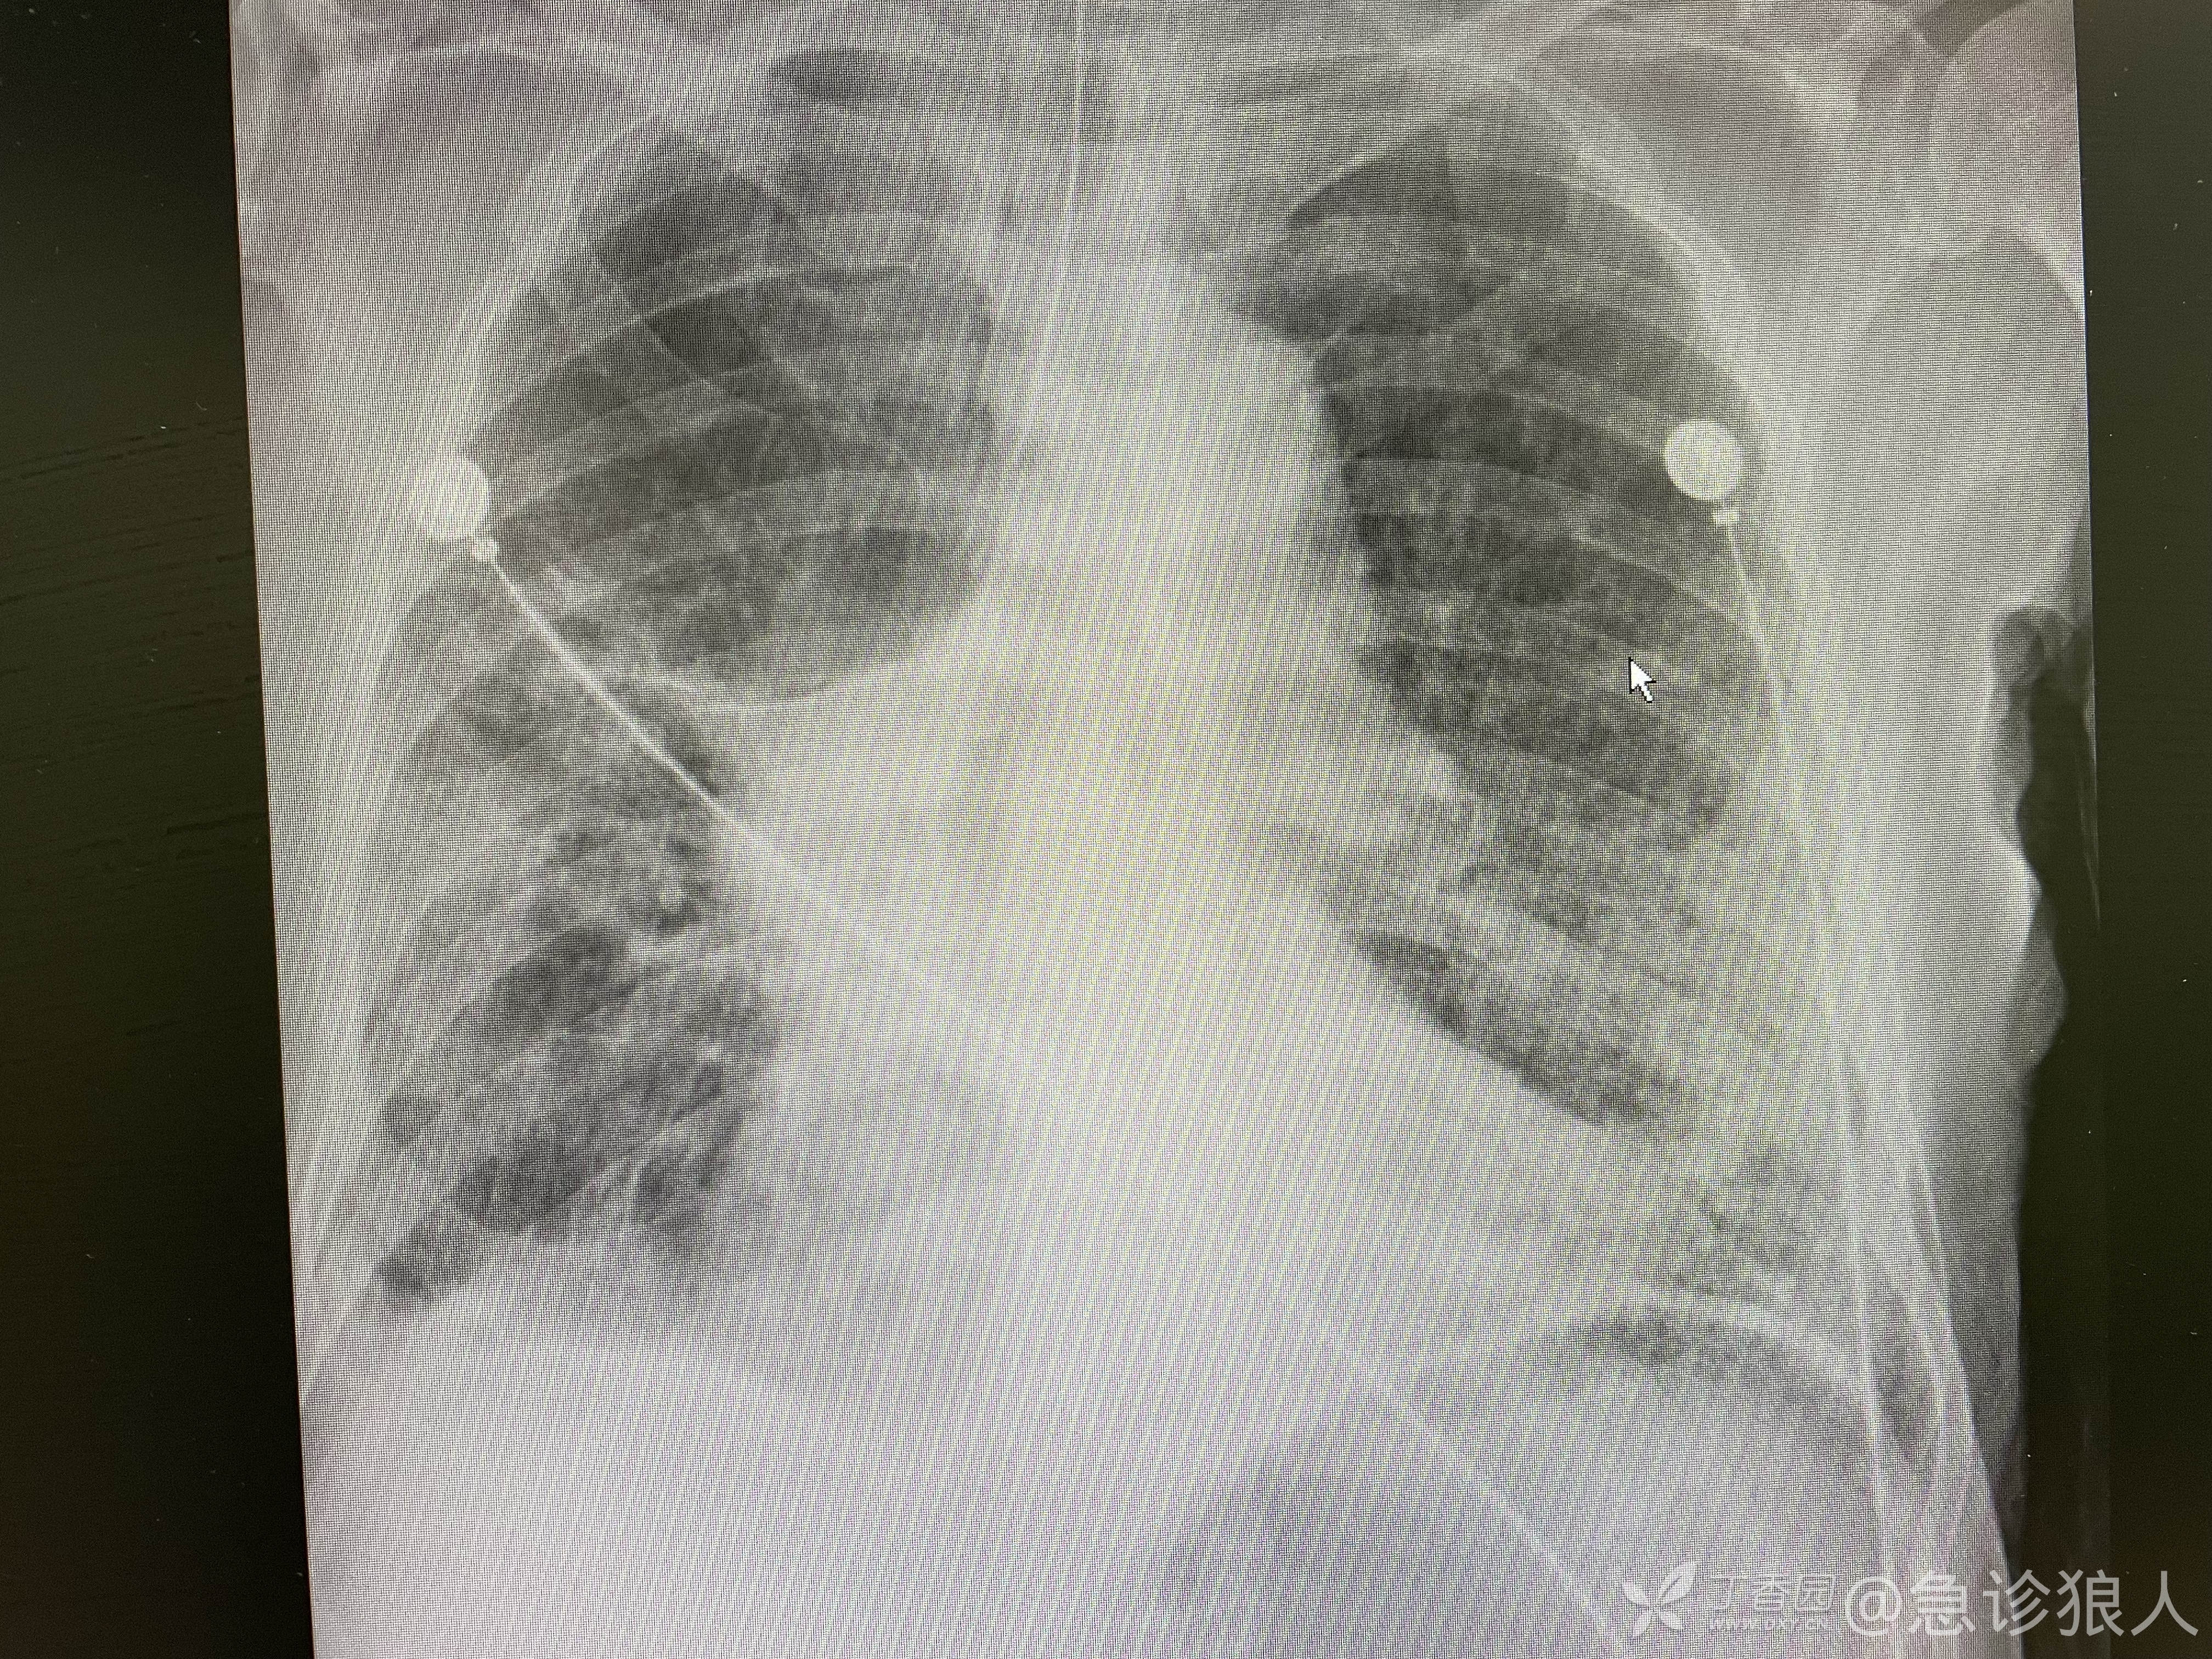

很快,患者的血、胸片全出,如下:

pct正常,crp158,应该就是肺部感染加重了,一口痰憋的,插管时就证明了。